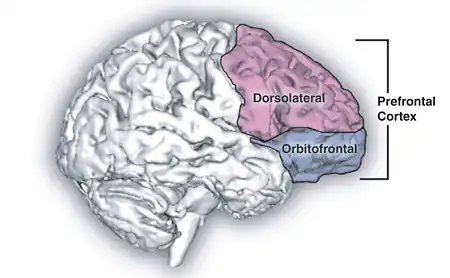

Images from neurological research can create images that show regions in the brain accociated with feelings of sadness. Research can not state the exact cause for emotions, rather areas within the brain activated when emotions arise. There is still debate between the amount of genetic factors and environmental influences which contribute to activating these areas of the brain. It is unexceptional to experience emotion such as sadness, as it is part of human physiology. Hormones play a vital part in emotions. Some primary hormones are, Cortisol, a hormone related to stress, with contributes to poor intellectual functioning, negative affect and low health. Testosterone has a high contribution to sex and arousal, Oxytocin is a hormone which leads people to seek comfort in times of need, bonding tendencies to cope with issues in the world. Dealing with negative feelings requires a release in dopamine. Dopamine enhances functioning. Neuroimaging and neurological studies have found that sad facial expressions enhanced activity in the left amygdala and right temporal pole. Sad expressions activate the amygdala region and lesions’ in this region have demonstrated difficulty in recognising expressions. Emotional expression is learnt through the amygdala (Dolan,1999). Dopamine originator of Norepinephrine,which has resulted from tyrosine which comes from diet, comes from regions in the brain stem, the locus ceruleuis and lateral tegmentum. These regions send axons to the cerbellum, spinal cored and amygdala. This shapes conciousness and emotional response. A shortage in dopamine production can effect norepinephrine production. This results in lethargy and low levels of energy, which results in a struggle to get up and go. An excessive amount of dopamine can lead the psychotic moods (Mendius, 2008). Positron emission tomography (PET) studies of emotion have reflected that areas of the brain which have shown activity for sadness are bilateral inferior and orbitofrontal cortex. bilaterally in anterior cingulate,medial prefrontal, and mesial temporal cortex, as well as in brainstem, thalamus, and caudate/putamen (Lane et al,1997). Ekman and Friesen focussed on facial expressions and the human race being universal and without influence from cultural factors. Studies in this field find that infants exhibit expressions of anger, fear, happiness, sadness, surprise and disgust even in such beginning life (Lane et al,1997). Similar to Ekman and Friesens study with men and facial expression, Lane, Reiman, Ahern, Schwartz,& Davidson (1997), experimented on the brain activity and emotions. Using 12 neurologically and psychiatrically, between 18and 30 who were female participants Positron emission tomography was used to measure regional brain activity. There were 12 conditions for each participant, happiness, sadness, and disgust and three control conditions, each induced by film and recall. Emotion and control tasks were alternated throughout. Condition order was pseudorandomized and counterbalanced between the particpants. For each emotion and control condition the brain regions were examined. Results support that varying brain regions are responsible for various emotion.